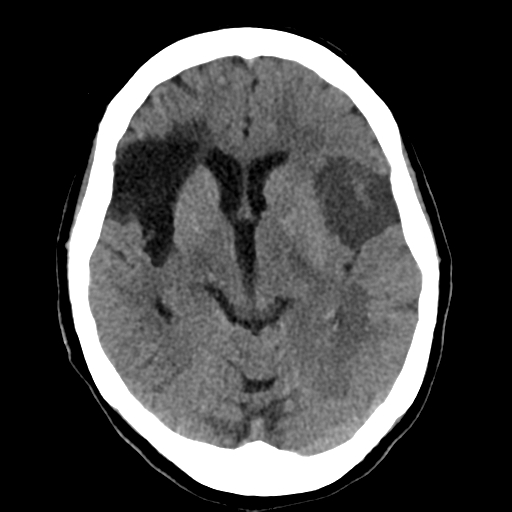

Se presenta el caso de paciente femenina de 69 años con antecedente de hipertensión arterial y enfermedad vascular crónica, quien consulta al servicio de emergencia por inicio súbito de debilidad en el hemicuerpo derecho asociada a dificultad para hablar y desviación de la comisura labial, síntomas de pocas horas de evolución.

Ante la sospecha clínica de evento vascular cerebral agudo, se realiza tomografía cerebral simple de urgencia.

El estudio demuestra una extensa área de hipodensidad cortico-subcortical en la región frontoinsular izquierda, con dimensiones aproximadas de 35 × 31 × 40 mm, hallazgo compatible con evento vascular isquémico agudo en territorio de la arteria cerebral media izquierda. Asociado a este hallazgo se identifica una pequeña hipodensidad subcortical en la región parietal izquierda, sugestiva de evento vascular isquémico agudo de menor extensión.

De forma adicional, en el hemisferio cerebral derecho se observa extensa área de encefalomalacia frontoparietal con extensión a la región insular, hallazgo compatible con evento vascular isquémico crónico, lo que sugiere antecedente de infarto cerebral previo.

No se identifican colecciones hemorrágicas intracraneales ni efecto de masa significativo al momento del estudio.

Se observan además pequeños granulomas calcificados corticales frontales y parietales bilaterales, compatibles con secuelas de neurocisticercosis en fase nodular calcificada, así como calcificaciones ateroescleróticas en las arterias intracraneales. También se identifican cambios cerebrales involutivos propios de la edad, caracterizados por leve dilatación ventricular y prominencia de surcos corticales.

Este caso ilustra una presentación de evento vascular cerebral isquémico agudo en el contexto de enfermedad cerebrovascular crónica, donde la tomografía cerebral simple permite identificar lesiones isquémicas recientes, descartar hemorragia intracraneal y evidenciar secuelas de eventos vasculares previos, información fundamental para orientar el manejo clínico inmediato.